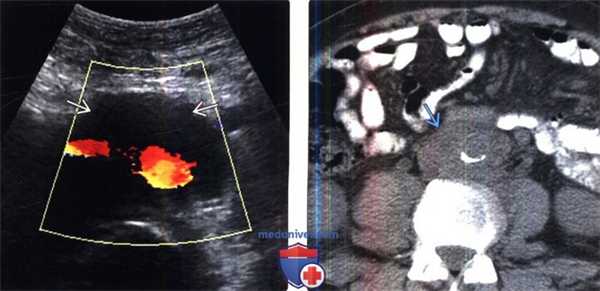

(Слева) УЗИ, поперечная плоскость: визуализировано мягкотканное образование, окружающее аорту и НВП при НХЛ.

(Справа) Бесконтрастная КТ, аксиальная проекция (этот же пациент): пораженные лимфатические узлы при НХЛ заполняют парааортальное пространство и смещают аорту от позвоночника.